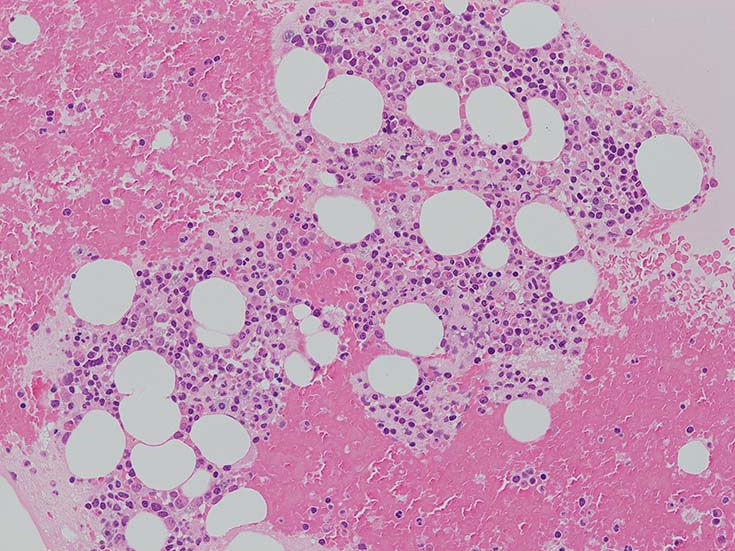

lymphoplasmacytic lymphoma(LPL)

検診異常の再検査で受診, 慢性炎症, 小球性貧血, 血清IgM高値あり. 造血器疾患を疑われ血液内科で精査となった.

IgG 1365mg/dl, IgA 225mg/dl, IgM 1800(35-220)mg/dl. 血清免疫電気泳動で IgM-λtype M proteinを検出. 尿中 Bence Jones タンパク-λ型(+).

この症例では骨髄組織での造血巣内にリンパ球や形質細胞の軽度増加があるようだが, 腫瘍細胞増殖が明瞭ではない. 結節形成はみられない. mast cellsの増加がNaphtol-ASD-CAE染色で確認される.